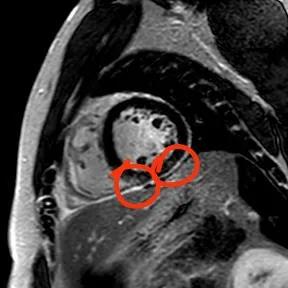

“快!做磁共振觀察心肌有無(wú)受損及程度?!庇跋裨\療中心陳寶瑩副主任為小燁進(jìn)行心臟磁共振平掃及增強(qiáng)掃描。結(jié)果提示:患者有急性心肌損傷,考慮心肌梗死。結(jié)果驗(yàn)證了小燁的心肌大片區(qū)失活。

方向比努力更重要,對(duì)于醫(yī)生而言更是如此,準(zhǔn)確把握病因方向,才能有效治療。心臟磁共振,成為非侵入性診斷心肌疾病的金標(biāo)準(zhǔn),能準(zhǔn)確地鑒別心肌炎、應(yīng)激性心肌病、心肌病淀粉樣變性、擴(kuò)張性心肌病及心肌梗死等,并能對(duì)心肌梗死后心肌纖維化進(jìn)行定量評(píng)估。